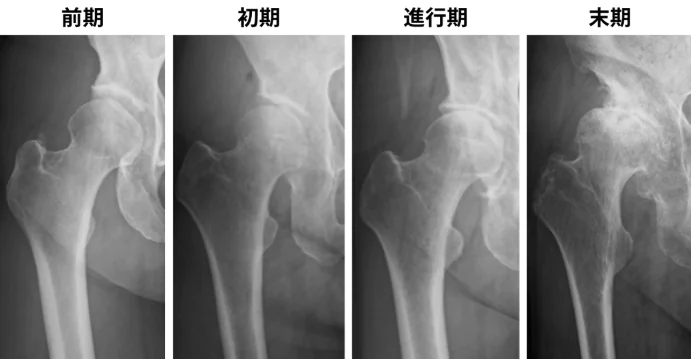

診断には患者さんの病歴・年齢・診察所見・画像検査などの情報で判断していきます。画像検査はまずレントゲン撮影が一般的で軟骨のすり減りの程度や関節の変形の程度を評価していきます。股関節痛の症状は腰から膝周囲まで広範囲に出現することもあるため、腰椎由来の症状の可能性も考慮し腰も含めて診察、診断していくこともあります。レントゲンでは変形性股関節症を認めるものの本当に股関節が痛いかどうかを判断するには股関節のブロック注射が有効です。手術など侵襲的な手技を行う前にはブロック注射による確定診断を行った上で治療を進めていくこともあります。